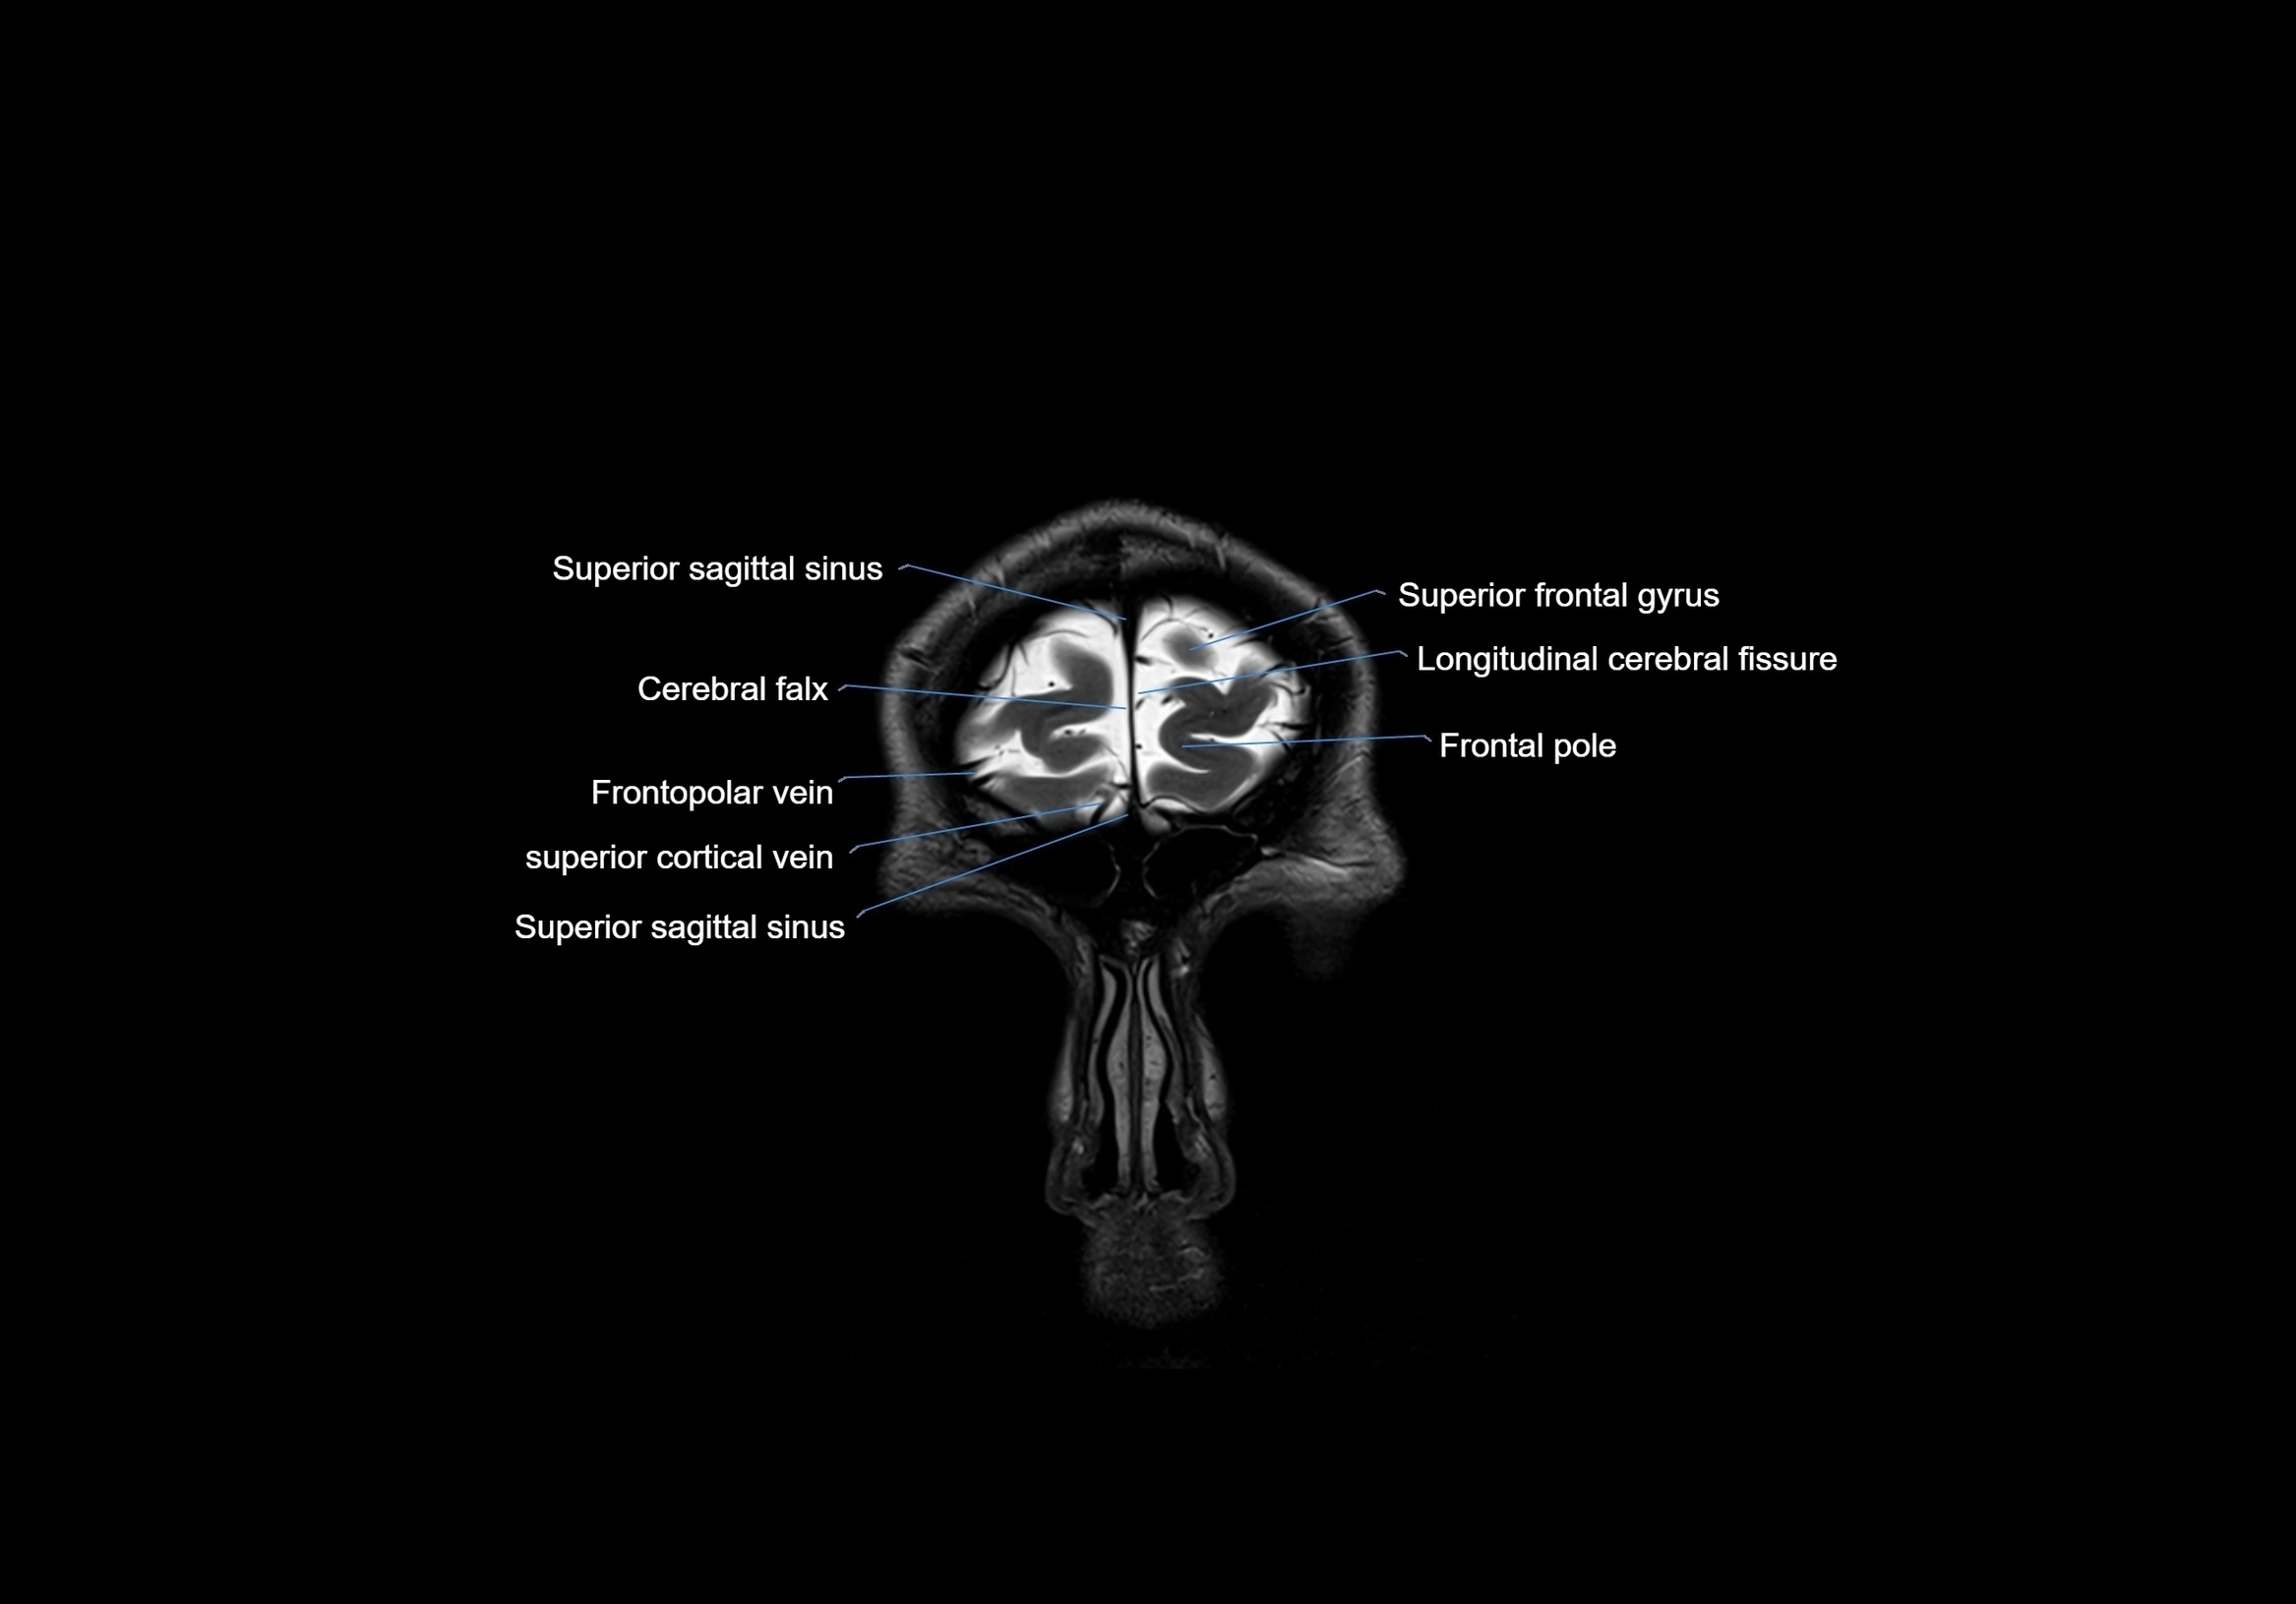

MRI images